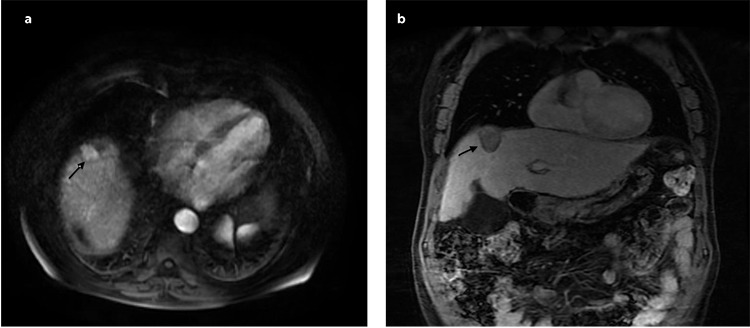

Methods: Between January 2019 and January 2022, percutaneous MWA procedures were performed for 50 liver tumors. These lesions were situated in close proximity to anatomically essential structures, with a maximum distance to surrounding structures being 10 mm. Because of comorbid lung diseases, patients could not undergo deep anesthesia. Regular follow-ups were performed using blood tests and dynamic contrast-enhanced computed tomography or magnetic resonance imaging.

Results: The patient cohort consisted of 30 (68%) men and 14 (32%) women, with a mean age of 64.36±11.65 years (range: 40-80 years). The lesions were challenging to access and were located in proximity to critical structures such as the diaphragm (32, 64%), gallbladder (8, 16%), major vessels (5, 10%), and heart (5, 10%). During the follow-up period, 10 patients (23%) had local tumor recurrence and 14 (32%) had new primary foci in a different location and metastasis [liver (10) and non-liver organs (4)]. No major complications developed, and 21 of 44 patients experienced minor complications, which were treated with local medications during follow-up.